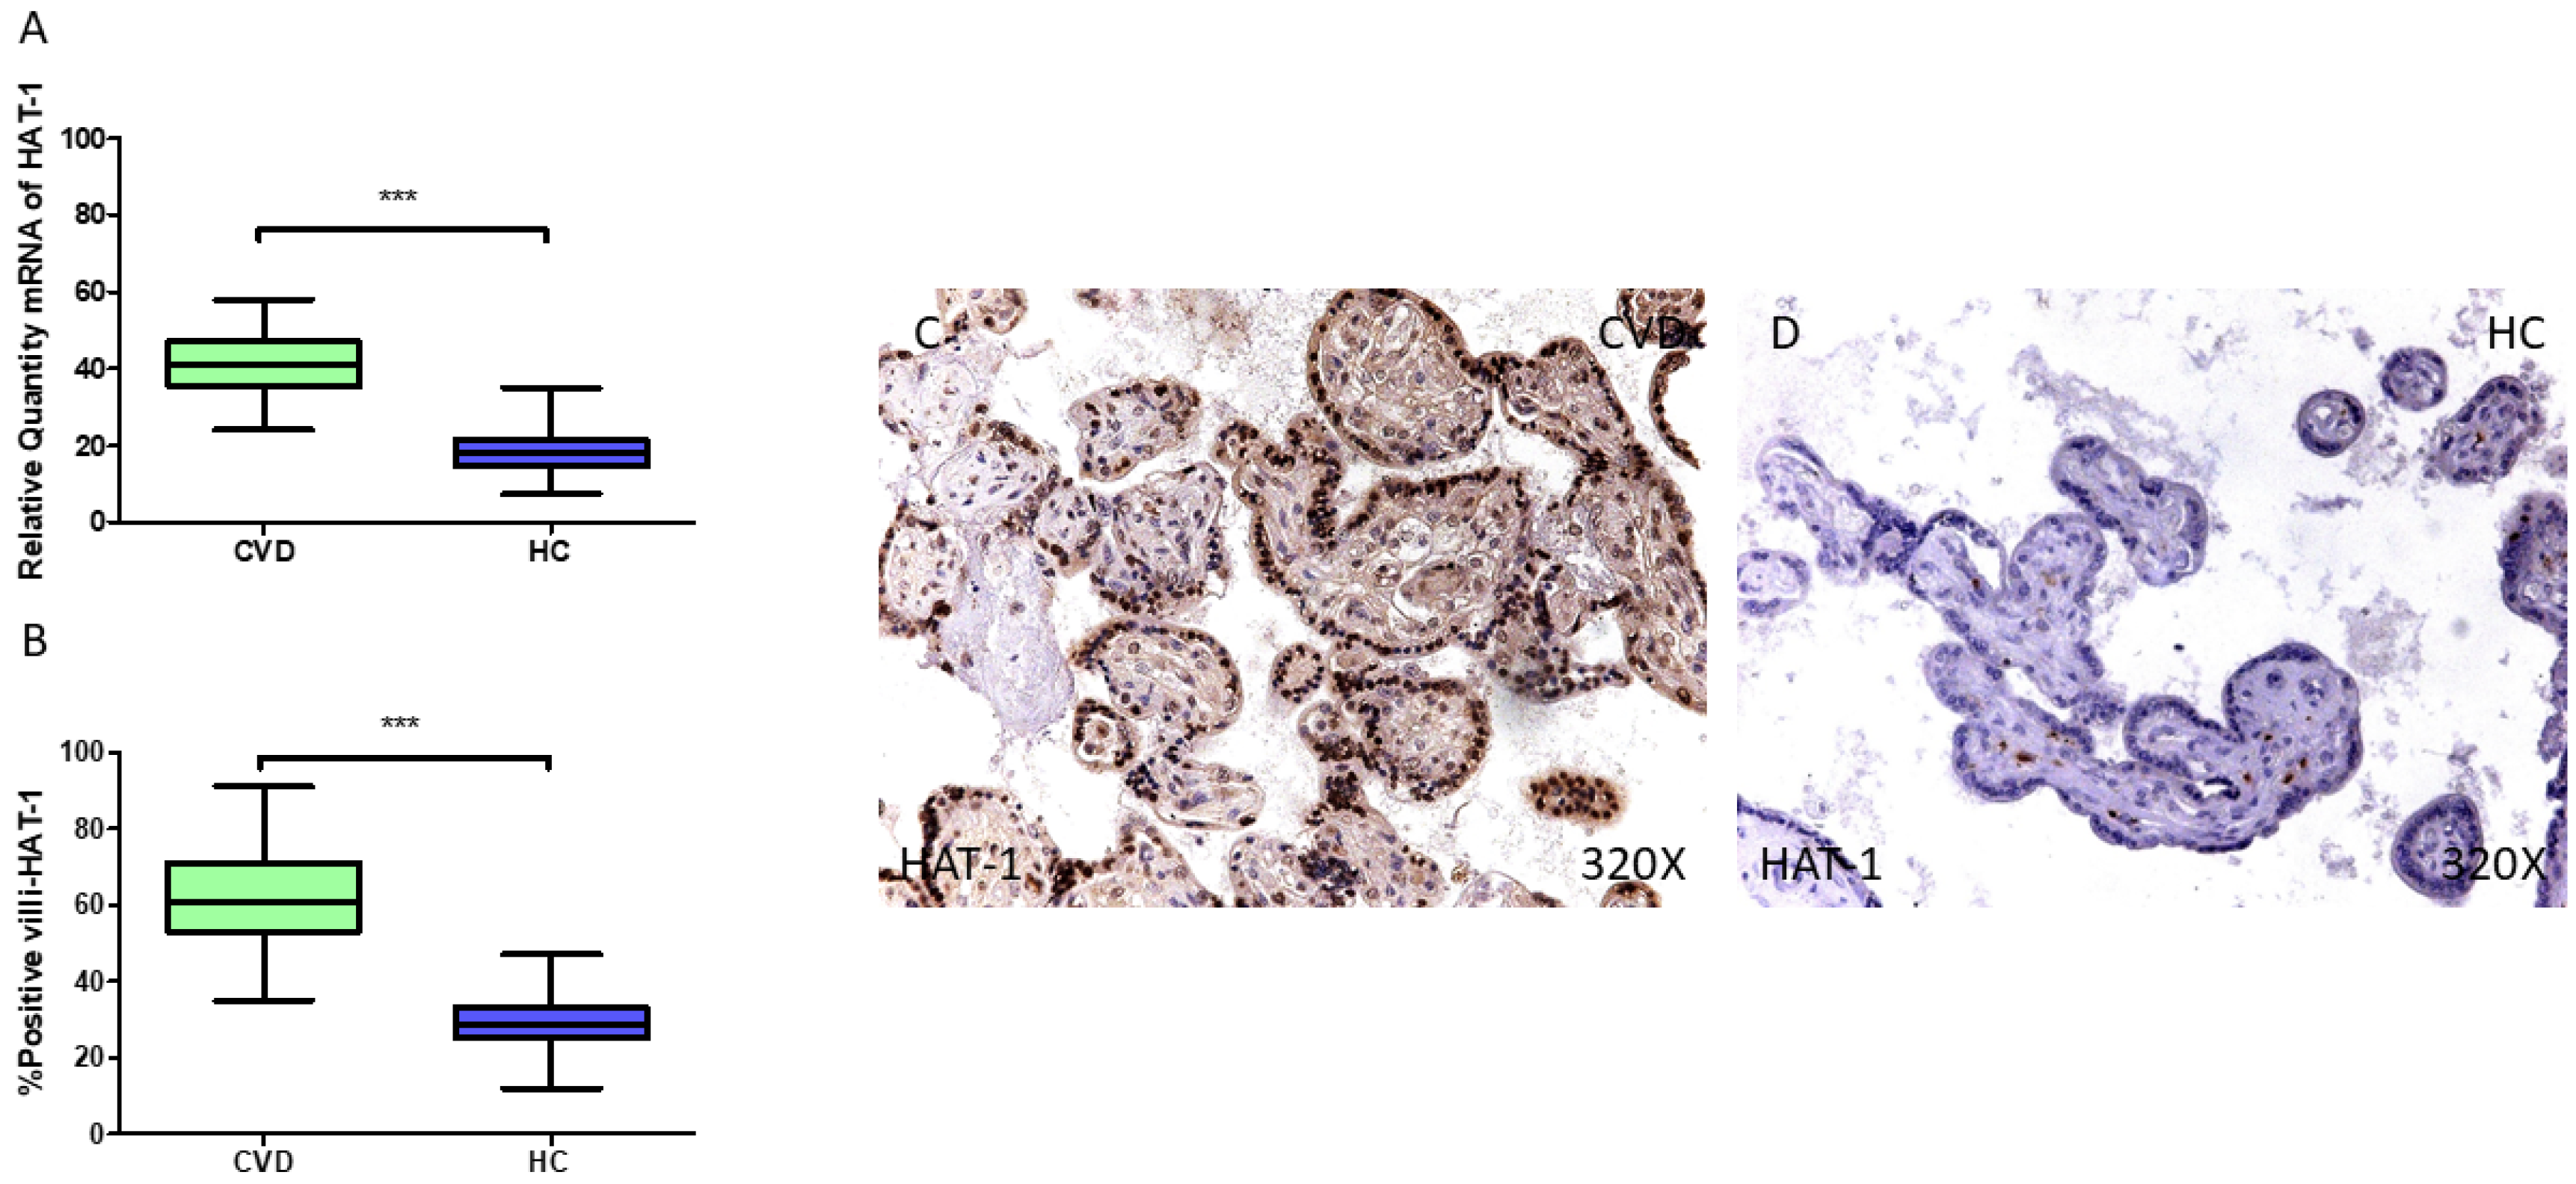

In parallel, our findings do support a significant rise in HAT1 gene expression in the placentas of the CVD-PW (*** p < 0.001; CVD = 41.036 [24.013–58.062], HC = 18.090 [7.300–35.055], Figure 6A). The histological analysis of the placental villi revealed a significant rise in Hat1 protein expression (%) in the chorionic villi of women with CVD (*** p < 0.001; CVD = 61.000 [35.000–91.000], HC = 28.500 [12.000–47.000], Figure 6B). Hat1 tissue expression was notably increased in all the placental villi of women affected by CVD compared to the HC, especially within the syncytiotrophoblast layer (Figure 6C,D).

Figure 6.

(A) HAT1 mRNA expression levels in pregnant females who were diagnosed with CVD compared to HC group (*** p < 0.0001). (B) IRS scores assessing HAT1 expression in placental tissue of women with CVD and without this condition (*** p < 0.0001). (C,D) Representative immunostaining images displaying HAT1 expression in placental villi from CVD and HC samples.